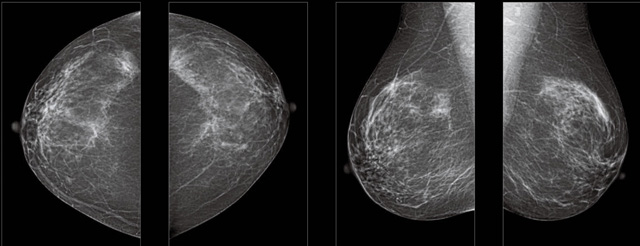

采用影像檢查技術來發現疑似特定病檢查跟人群的普查。一到兩年進行一次X光線的乳腺檢查。記過是C或者D型,可以加上B超協同。還可以一年一次核磁共振MRI檢查。70歲以上的女性認為絕經的女性是比較安全的。實際上也有乳腺癌的風險。65歲以上風險也很大。也是需要進行機會性篩查。

2,乳房自檢在發現有異常情況下借助科學影像乳腺超聲設備檢查,進一步明確診斷,可以檢查到臨床觸摸不到的腫塊的早期乳腺癌。乳腺DR的檢查早期乳腺癌的診斷率更高。鑒別惡性、良性腫瘤的準確率可以有90%以上。可以讓乳腺癌死亡率降低很多。乳腺DR還可以跟鉬靶X光射線檢查配合,無毒無害無輻射。還可以鑒別囊乳腺增生等其他乳腺疾病。

乳腺DR超聲報告的乳腺結節是一個描述的語言,形容發現的腫塊。不涉及腫物的良性惡性性質也不是疾病的名稱。結節是低回聲還是無回聲,邊界清楚還是邊界不清楚是形容這些結節在圖像上清晰問題。不能來判斷良性惡性的。還需要醫生的具體分析。結構紊亂可能跟乳腺增生有關。囊腫同樣在超聲報告中經常顯示。多數的囊腫是良性無害的。BI-RADS 大于等于三級時候就需要醫生特別重視,進行進一步的診斷或者外科干預了。鈣化也比較常見,惡性的很低幾率。可疑的惡性鈣化就需要醫生進一步的處理。